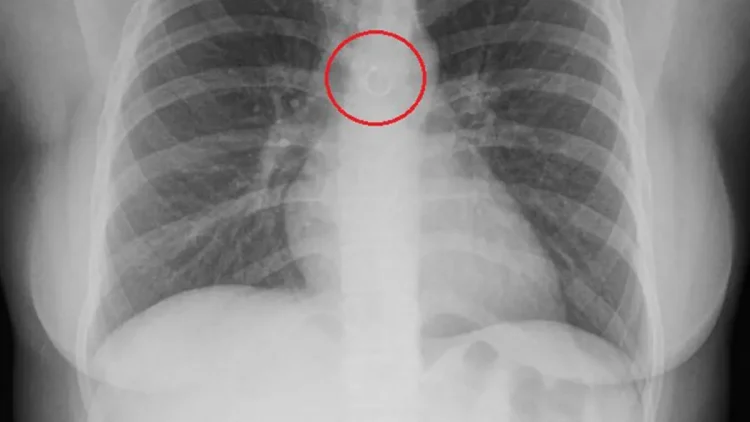

Monica Deyanira Cabrera Barajas had developed an annoying cough for about a month when she decided to see a doctor about it. She expected the X-ray to reveal a problem, but what she definitely didn’t expect to see was her nose piercing.

Deyanira’s initial shock soon turned into fear for her life, as the doctors told her that the circular metal barbell was just 0.5 millimetres from her aorta. She was scheduled for emergency surgery, but what was supposed to be a 20-minute procedure ended up taking almost an hour and a half and ended in failure.